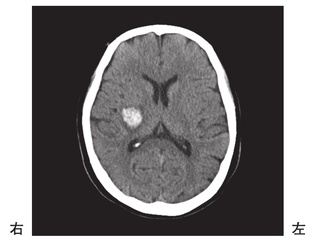

脳梗塞の発生部位によって出現する症状は異なります。この問題では、それぞれの部位における症状を正確に理解することが求められています。

右内包後脚では、左上下肢の運動麻痺が見られるため、この選択肢は正しいです。

Broca領域は運動性失語の症状が現れる部位であり、遂行機能障害は前頭葉で見られるため、この選択肢は誤りです。